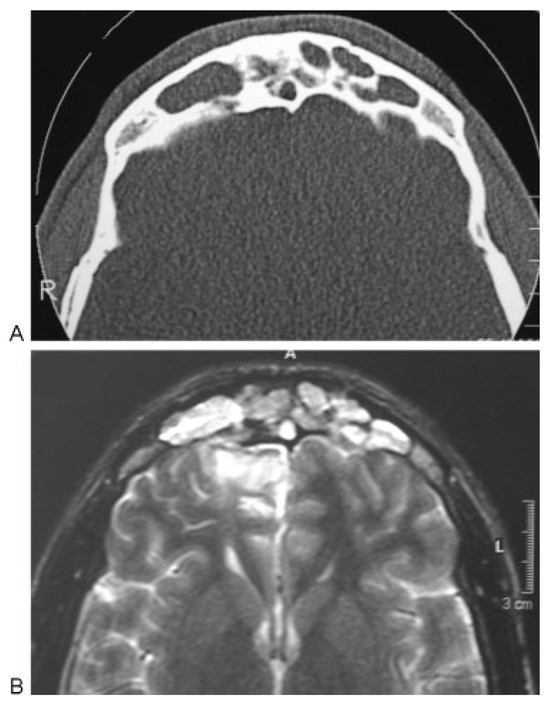

Natural Course of Orbital Roof Fractures

by Liselotte H. M. Stam, Eppo B. Wolvius, Warren Schubert and Maarten J. Koudstaal

Craniomaxillofac. Trauma Reconstr. 2014, 7(4), 294-297; https://doi.org/10.1055/s-0034-1378188 - 3 Jun 2014

The natural course of several isolated and nonisolated orbital roof fractures is reported, by showing four cases in which a “wait and see” policy was followed. All four cases showed spontaneous repositioning and stabilizing of the fracture within less than a year. This [...] Read more.

The natural course of several isolated and nonisolated orbital roof fractures is reported, by showing four cases in which a “wait and see” policy was followed. All four cases showed spontaneous repositioning and stabilizing of the fracture within less than a year. This might be explained by the equilibrium between the intraorbital and intracranial pressures. Full article